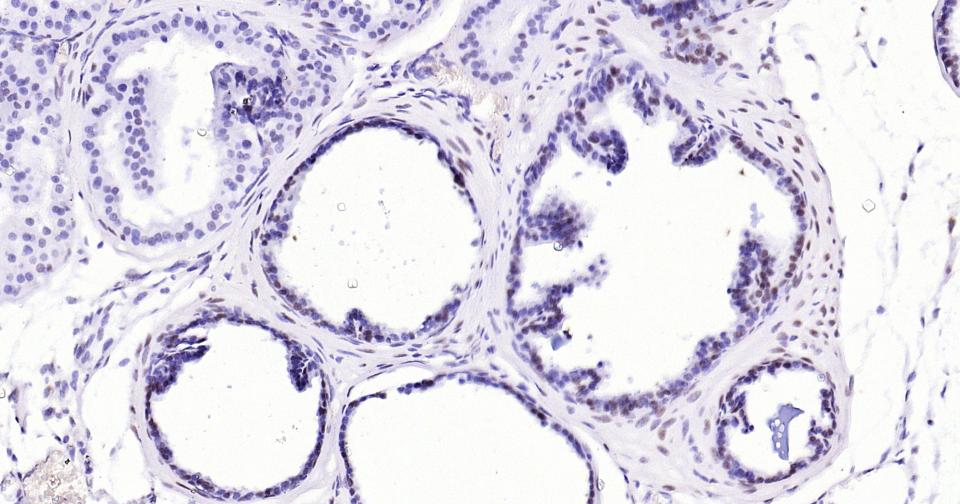

Paraformaldehyde-fixed, paraffin embedded Mouse Prostate; Antigen retrieval by boiling in sodium citrate buffer (pH6.0) for 15 min; Antibody incubation with Androgen receptor Monoclonal Antibody, Unconjugated(bsm-61204R) at 1:200 overnight at 4°C, followed by conjugation to the SP Kit (Rabbit, SP-0023)and DAB (C-0010) staining.